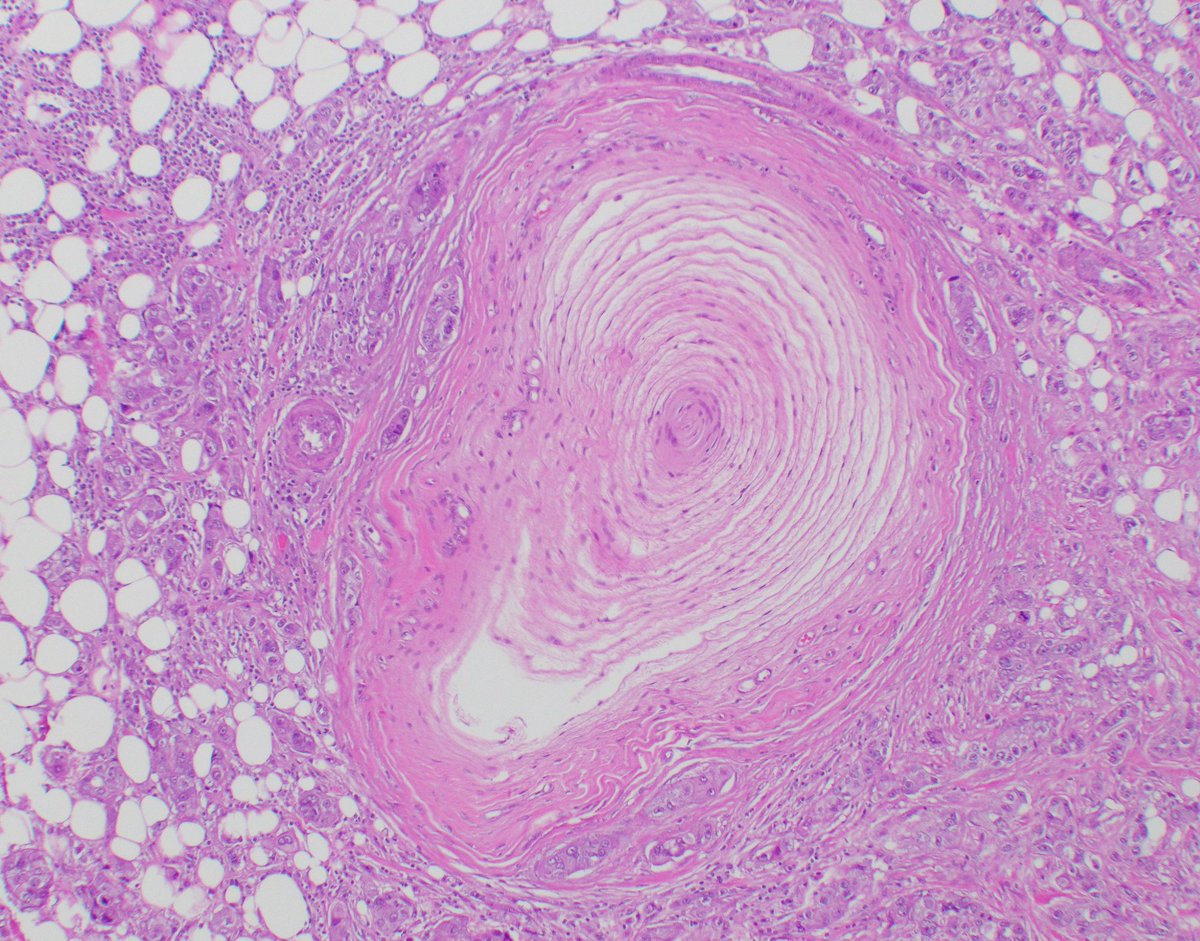

Skin lesion of a patient with hx of breast cancer s/p post-radiation: Angiosarcoma Infiltrative anastomosing vascular channels with endothelial atypia, preadnexal+perineural invasion. CD31+, ERG+, CK- #breastpath #pathresidents #pathtwitter #BreastPatholog1 Columbia Pathology ISBP

Skin lesion of a patient with hx of breast cancer s/p post-radiation: Angiosarcoma

Infiltrative anastomosing vascular channels with endothelial atypia, preadnexal+perineural invasion.

CD31+, ERG+, CK-